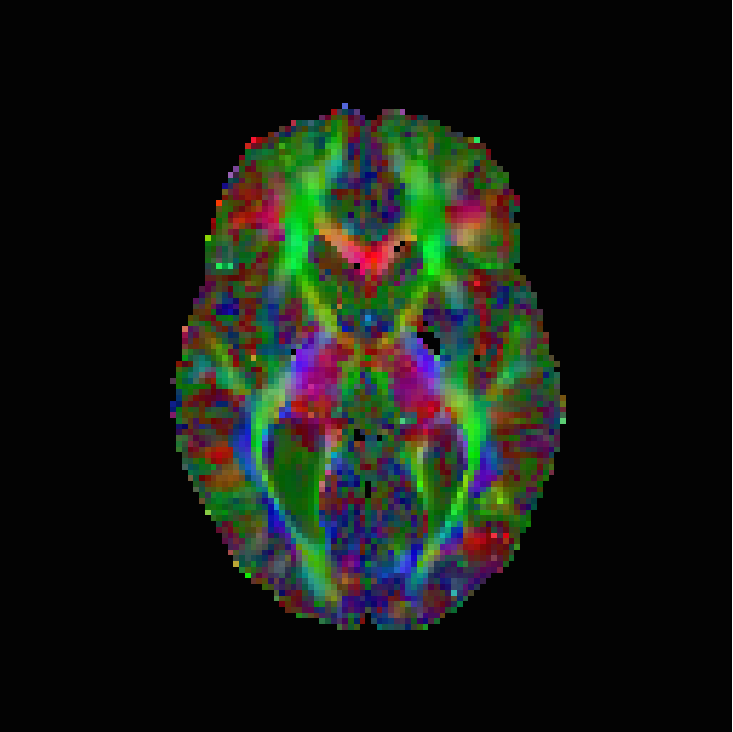

The numerical results are in Table 1 and Figures 3–5, with the first of the figures showing the colour-coded principal eigenvector of the reconstruction, the second showing the fractional anisotropy and principal eigenvectors, and the last one the errors in the latter two, in a colour-coded manner. All plots are masked to represent only the non-zero region. The field of fractional anisotropy is defined for a field of 2-tensors on as

As we can see, the non-linear approach (3.2) performs overall the best by a wide margin, in terms of the pointwise Frobenius error, i.e., error in . This is expressed as a PSNR in Table 1. What is, however, interesting, is that the constraint-based approach (3.5) has a much better reconstruction of the principal eigenvector angle, and a comparable reconstruction of its magnitude. Indeed, the 95% confidence interval in Figure 3(g) and Figure 4(g) suggests a nearly perfect reconstruction in terms of smoothness. But, the Frobenius PSNR in Table 1 for this approach is worse than the simple unregularised inversion by regression. The problem is revealed by Figure 5(f): the large white cloudy areas indicate huge fractional anisotropy errors, while at the same time, the principal eigenvector angle errors expressed in colour are much lower than for other approaches. Good reconstruction of the principal eigenvector is important for the process of tractography, i.e., the reconstruction of neural pathways in a brain. One explanation for our good results is that the regulariser completely governs the solution in areas where the error bounds are inactive due to generally low errors. This results in very smooth reconstructions, which is in the present case desirable as our synthetic tensor field is also smooth within the helix.

The results are in Table 2 and Figures 6–8, again with the first of the figures showing the colour-coded principal eigenvector of the reconstruction, the second showing the fractional anisotropy and principal eigenvectors, and the last one the errors in the latter two, in a colour-coded manner. Again, all plots are masked to represent only the non-zero region. In the figures, we concentrate on error bounds based on 95% confidence intervals, as the results for the 90% and 99% cases do not differ significantly according to Table 2.